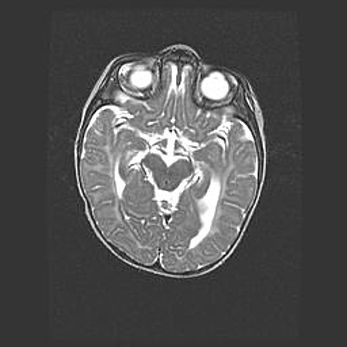

Ниже представлена  галерея МРТ снимков, полученных с применением LMT неонатальных матричных РЧ катушек. Также каждая группа МРТ снимков сопровождается информацией о пациенте (диагноз, возраст, вес, пол, срок гестации) и краткой сопроводительной расшифровкой диагноза.

Церебральная ишемия II.

Возраст: 5 дней

Вес: 3400 г

Пол: женский

Окружность головы: 35 см

Срок гестации: 39 недель

Церебральная ишемия – это заболевание, характеризующееся недостаточностью (гипоксией) либо полным прекращением (аноксией) снабжения мозга кислородом по причине закупорки одного или нескольких сосудов. Это приводит к  что метаболическим расстройствам различной степени тяжести в тканях головного мозга, развитию коагуляционных некрозов и гибели нейронов.